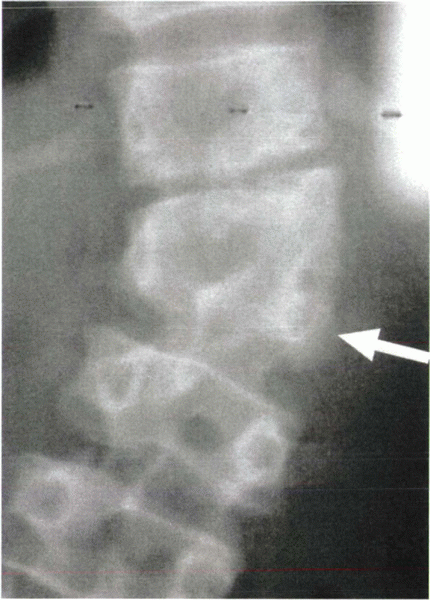

Figure 19-2 Radiograph showing a semisegmented hemivertebra (arrow).